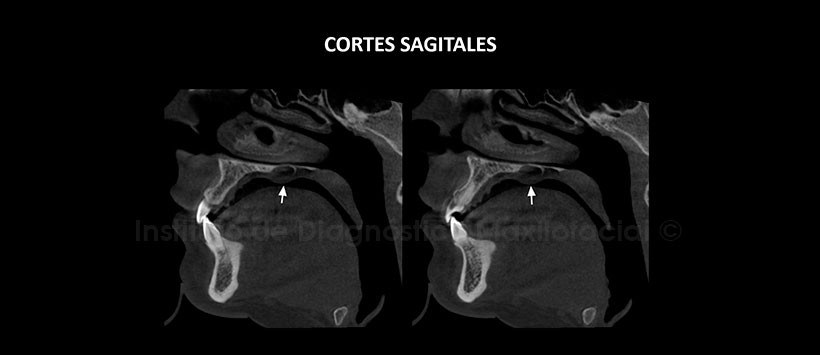

A la evaluación de la tomografía volumétrica (CBCT) mediante cortes axiales (Figura 2), coronales (Figura 3), sagitales (Figura 4), se evidencia una lesión hipodensa de límites definidos, bordes corticalizados, localizado en el lado izquierdo del tercio medio del paladar duro. La lesión ocasiona desplazamiento y adelgazamiento del piso de fosa nasal, así como del contorno medio basal del seno maxilar, se aprecia además un aumento del tejido blando adyacente